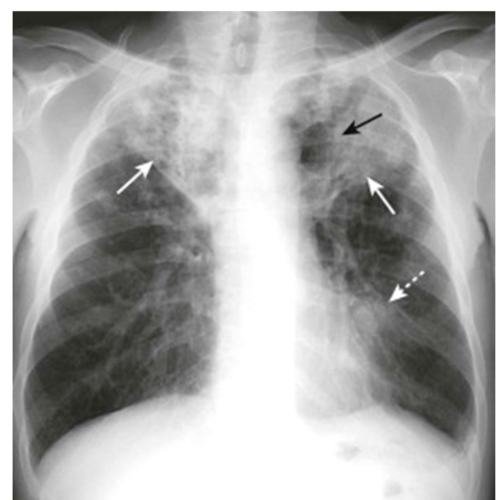

How does reactivation of TB look like in CXR?

• Solid white arrows show cavitary upper lobe pneumonia → it is considered TB unless proven otherwise

• Dashed arrow shows hilar lymphadenopathy

• Black arrow is lucencies in airspaces